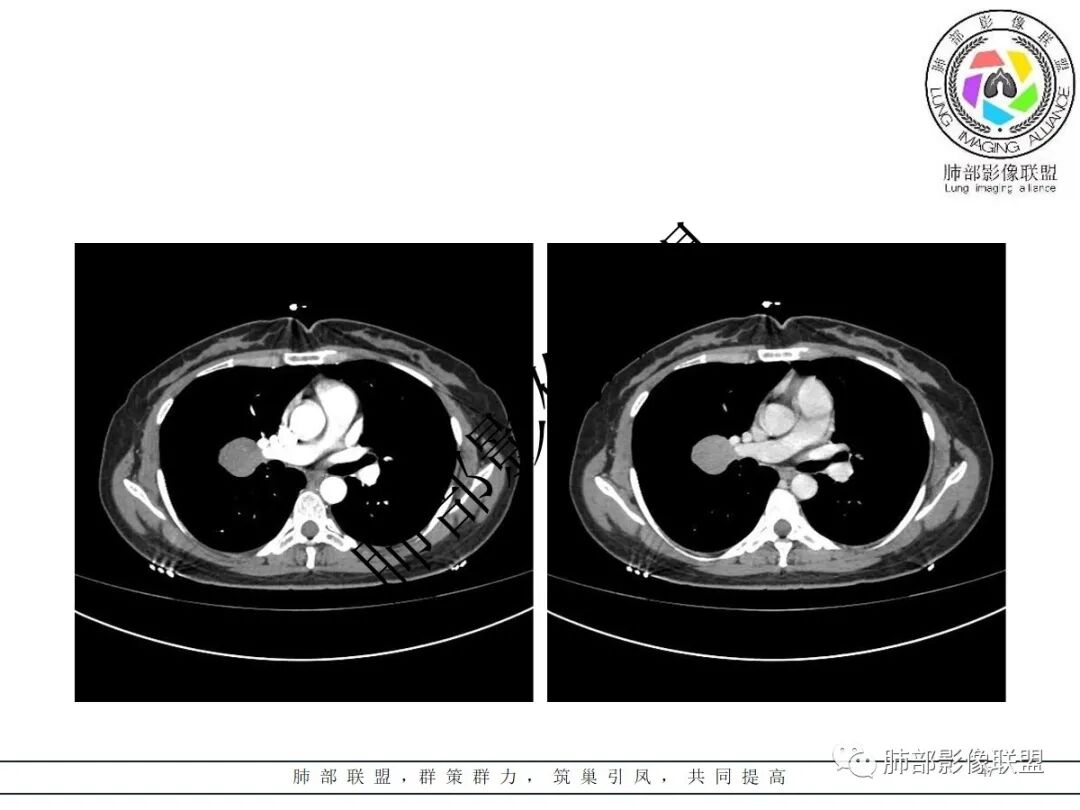

3.病灶密度均匀,未见液化坏死、钙化及脂肪低密度。轻度强化,可见纤细血管影蜿蜒穿行。右肺动脉推移变形,未见侵入或充盈缺损。

1.相对孤立表面光整无分叶块影或结节影,与支气管无关,肺门及纵隔未见增大淋巴结。

3. 良性病灶好发部位由外而内排个序:孤立性纤维瘤(SFT)、硬化性肺细胞瘤(PSP)、错构瘤、巨淋巴结增生症(CD)等。

1)巨淋巴结增生症(CD)大多动脉期高强化,毕竟透明血管型占多数,本例特征不足。

3)硬化性肺细胞瘤(PSP)可以血管贴边,常常强化比较显著。

4)发生于肺表面(近脏层胸膜或叶间裂),强化不显著,可见穿行血管,与本例的符合程度是最高的。